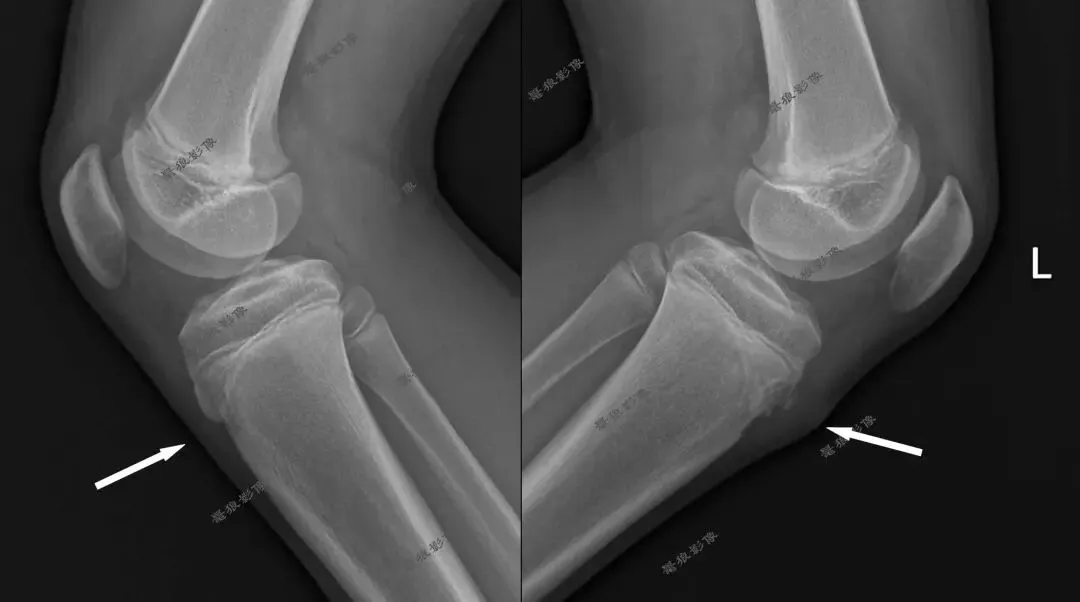

M,13y。左膝疼痛月余,近日加重就诊。

X线平片(双侧):

X线平片(放大)

考虑左胫骨结节骨软骨炎,请结合临床,建议进一步检查。